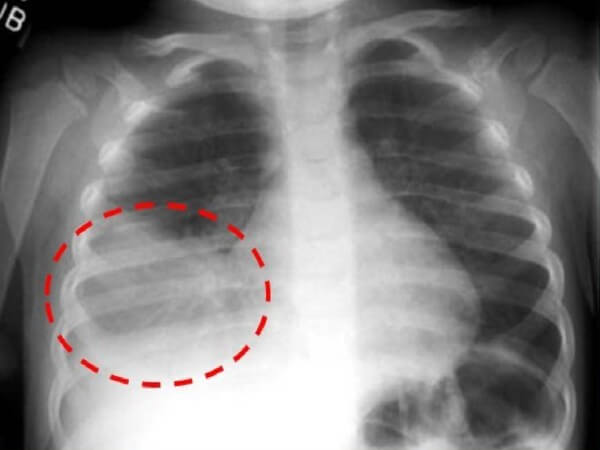

Нижнедолевая форма

В нижней доле правого легкого чаще всего скапливаются вирусы и бактерии, из-за его косого направления. Особенностью нижнедолевой пневмонии у детей является её быстрое прогрессирование. Без грамотного лечения уже через несколько дней на месте очагового инфильтрата появляется сегментарный или долевой очаг.

Нижнедолевая правосторонняя пневмония

Диагностика

Диагностика правосторонней пневмонии основывается на клинической картине, аускультативных и лабораторных симптомах.

К необходимым обследованиям при подозрении на воспаление лёгких относят:

- осмотр врача-педиатра;

- рентгенография органов грудной клетки в прямой и боковой проекциях;

- общий анализ крови;

- микроскопия мокроты, её бактериологический анализ для определения чувствительности возбудителя к антимикробным препаратам.